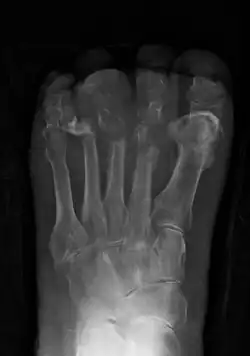

| Osteomyelitis of the 1st toe | |